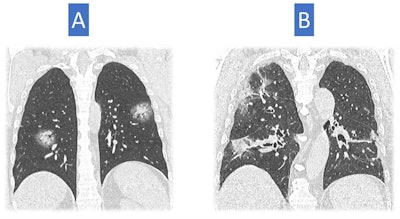

In the first two weeks of the pandemic (29 February to 13 March), the majority of the 806 CT scans performed showed typical positive findings (549 patients, or 68%) and a sizeable proportion had negative CT results, i.e., normal or highly suggestive of an alternative diagnosis (179, or 22%). A total of 78 scans (10%) were indeterminate.

With time, there was a shift in the proportion of positive and negative scans: There was a sizeable proportion of negative and indeterminate CT scans in the first week of March, but the proportion of positive cases and severe disease at CT increased drastically in prevalence toward the middle of the month.

"CT at the beginning was very valuable for differential diagnoses and helping clinicians interpret the clinical findings. But in the new endemic environment, the likelihood of seeing classic COVID-19 pneumonia is high," he said, pointing to a trend of increasing chest x-ray for classical clinical presentation of COVID-19 pneumonia.